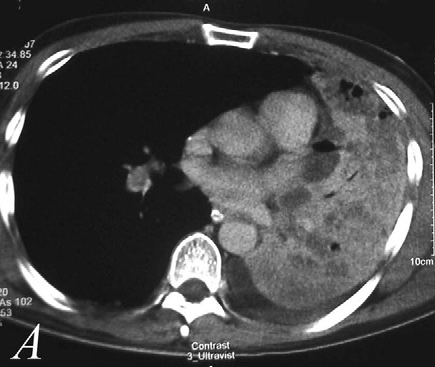

- Mediastinal strukturlara yayılmanı dəqiqləşdirmək üçün KT və endobronxial USM ilk seçimdir (Şəkil 11).

- Uzaq metastazaları təyin etmək üçün ilk növbədə abdominal KT (böyrəküstü vəzə və qaraciyərə yayılmanı qiymətləndirmə) edilir, sümüklərə və beyinə metastazı yoxlamaq üçün PET-KT tətbiq edilir.

Şəkil 11. Ağciyər xərçənginin diaqnostikası (KT).